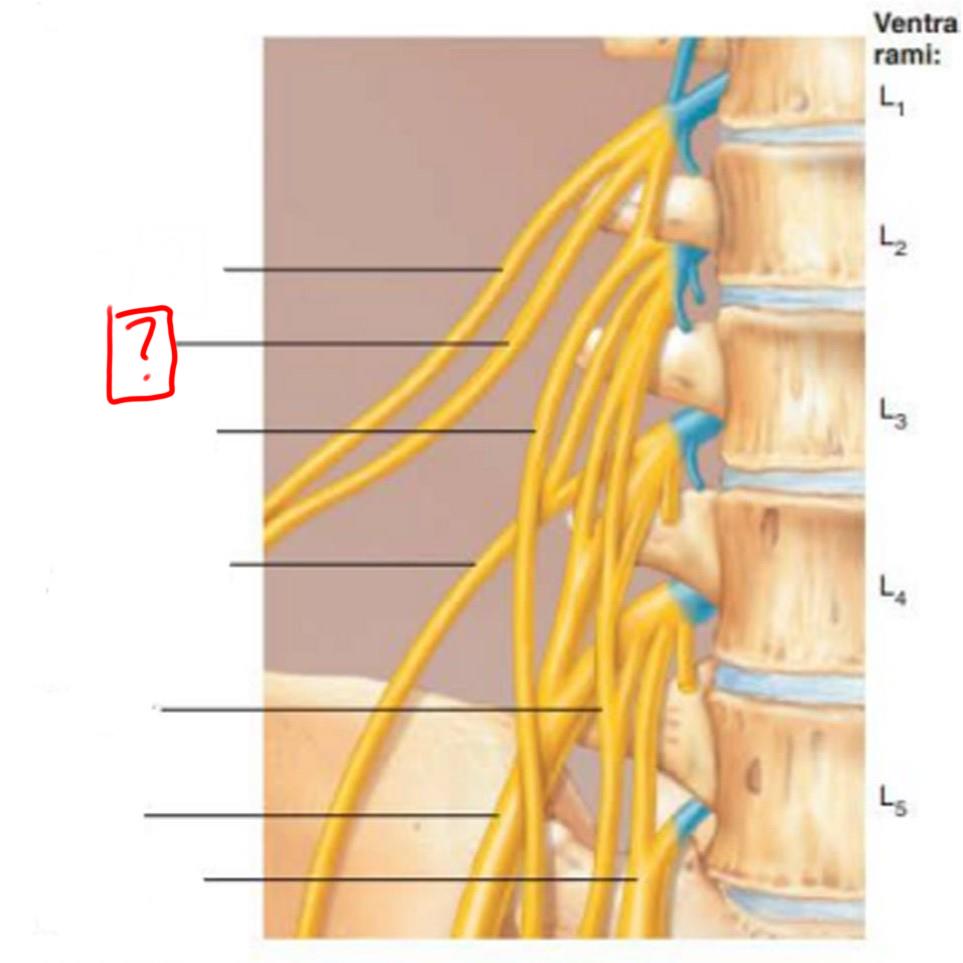

lumbar plexus

L1-L4

major nerves: ilioinguinal, obturator, femoral, genitofemoral

iliohypogastric

ilioinguinal

genitofemoral

lateral femoral cutaneous

obturator

femoral

lumbosacral trunk